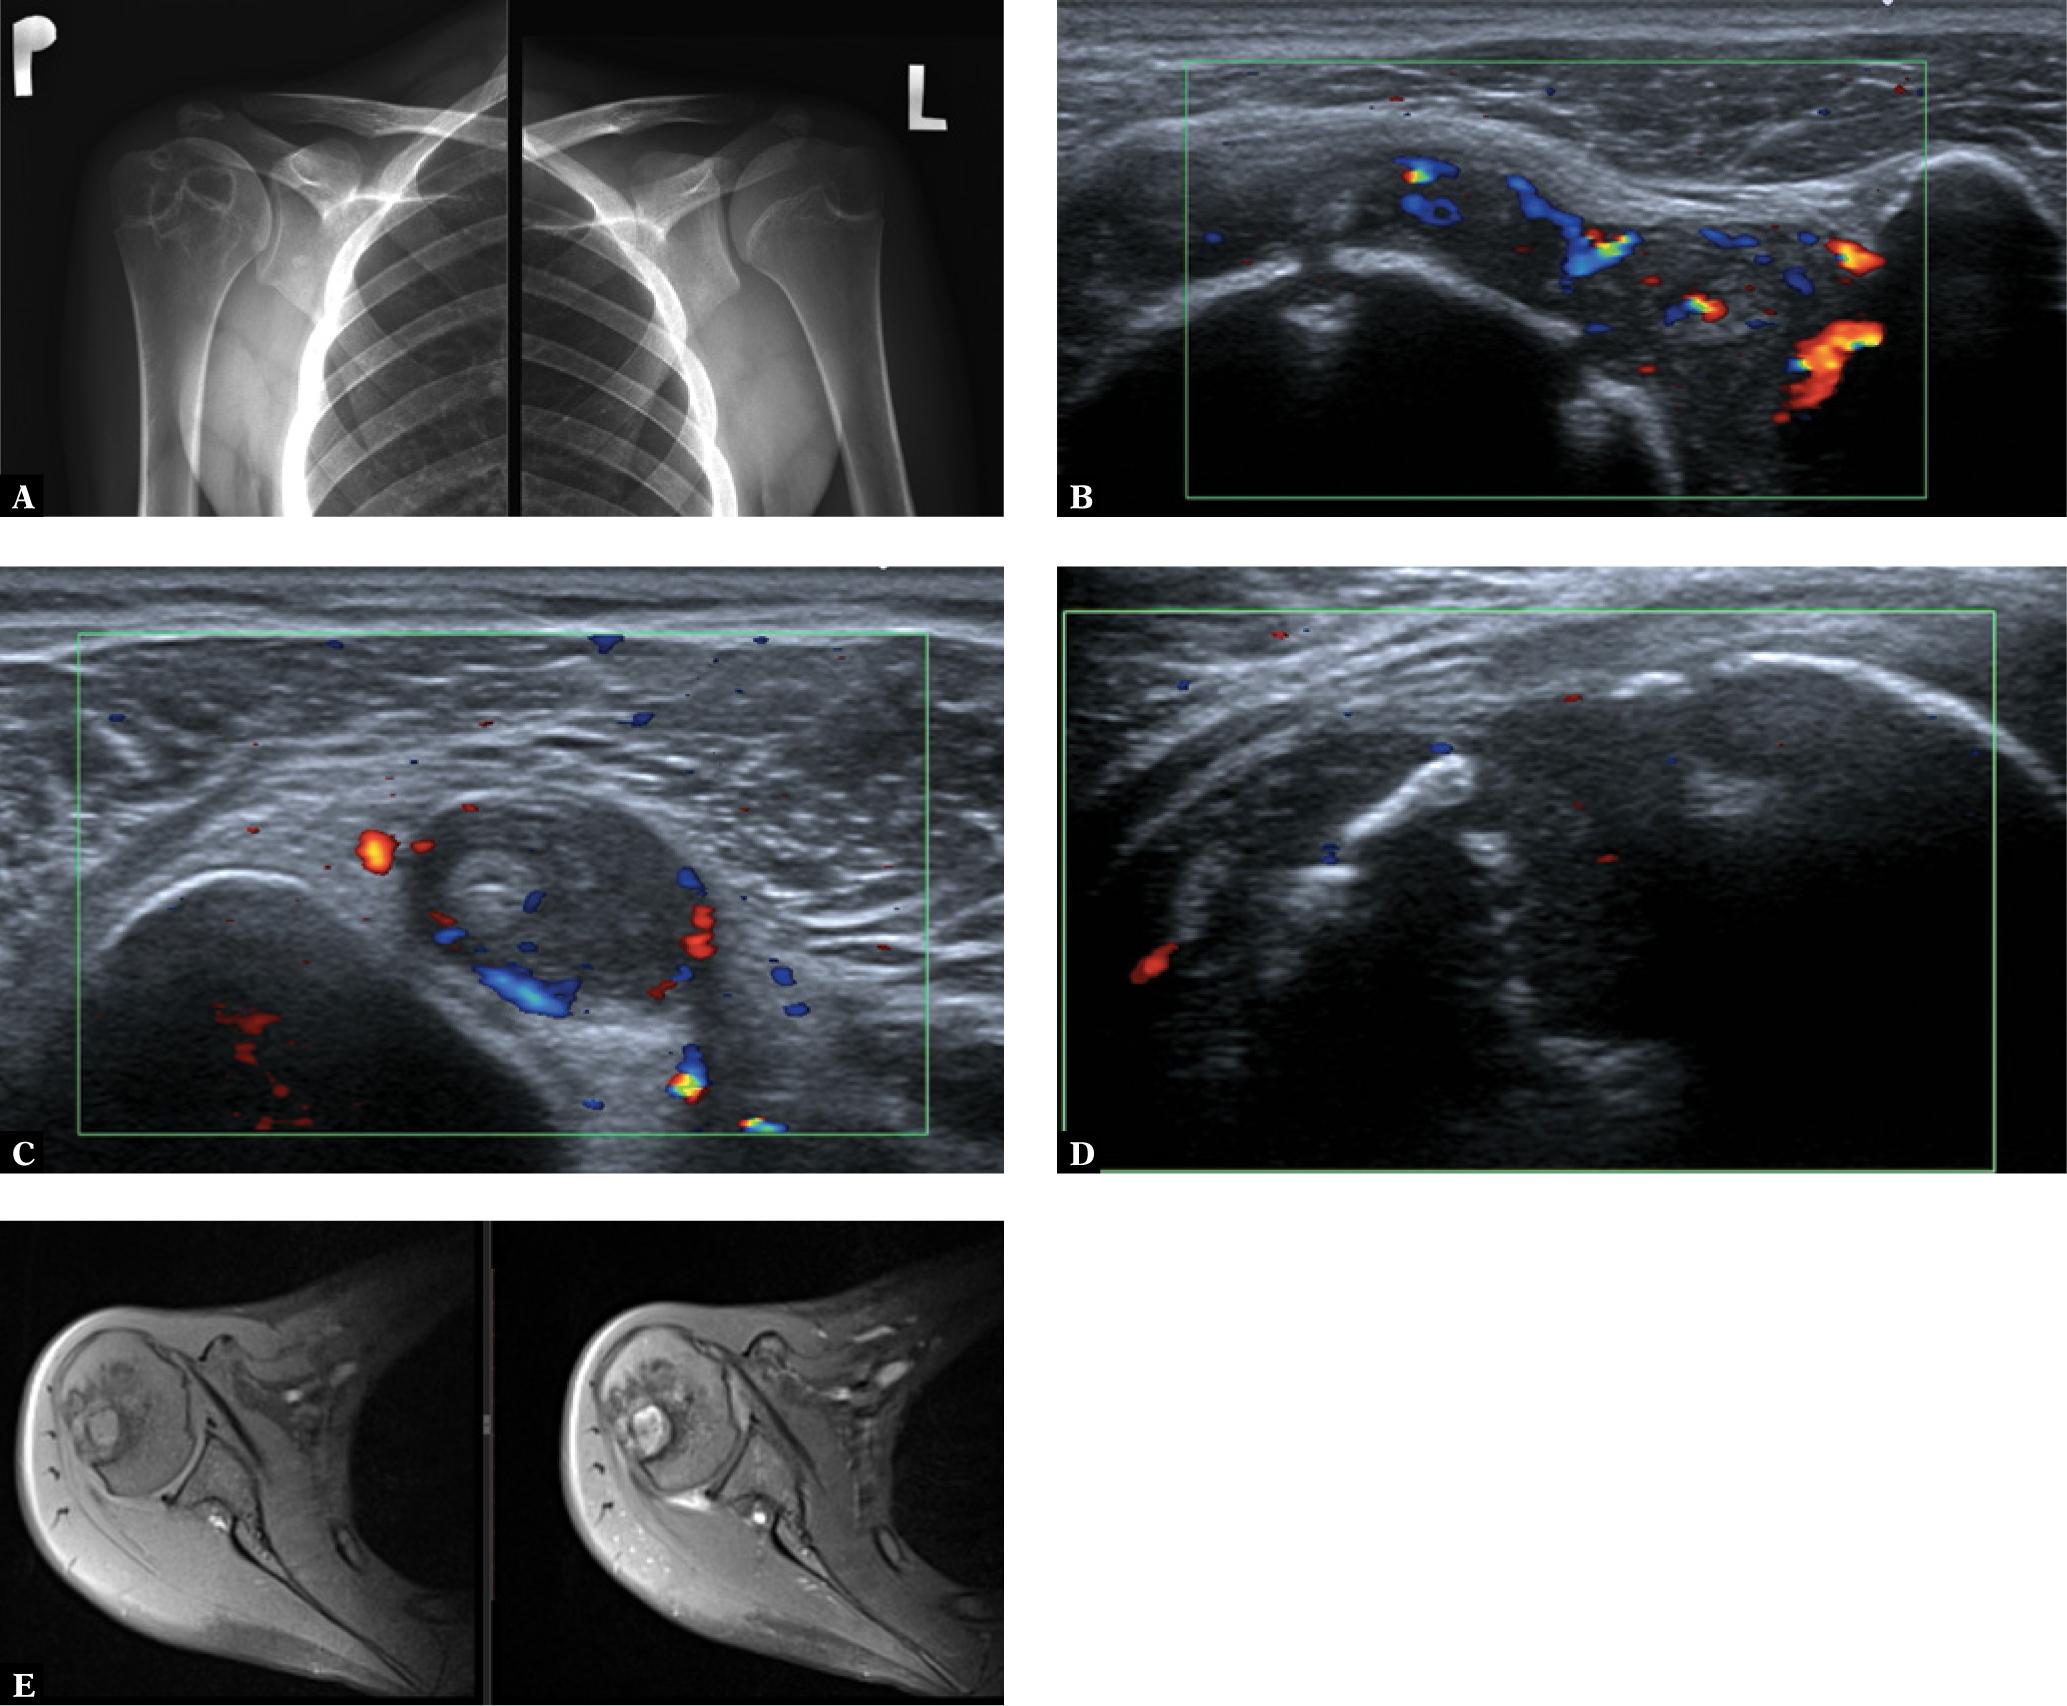

Arthritis is the most common extra-intestinal manifestation of IBD(16). This disease occurs in approx. 10% of children with inflammatory bowel disease(16,34,35). There are 2 main subtypes of this form of JSpA: more frequent peripheral form, associated with peripheral joint arthritis, and the more rarely occurring axial form, with involvement of the sacroiliac joints and the spine. The peripheral form usually involves the large joints of the lower limbs, typically the knee and ankle, more rarely the wrists, hands, and shoulders (Fig. 7), usually in an asymmetrical manner(16).

Glenohumeral joint US and MRI in a 17-year-old boy with Crohn’s Diseases: A. an AP radiograph shows numerous cysts in the right humeral head and medial aspect of the neck of the humeral bone, left joint is normal; ultrasound (B–D) shows active synovitis and two small erosions of the humeral head (B), tenosynovitis of the long head of the biceps tendon and (C), deep inactive erosion of the humeral head (D); an MRI T1-weighted fat-suppressed (FS) (E) and postcontrast T1-weighted FS (F) images show BME, a large cyst, multiple erosions, and a postcontrast signal increase within inflammatory lesions